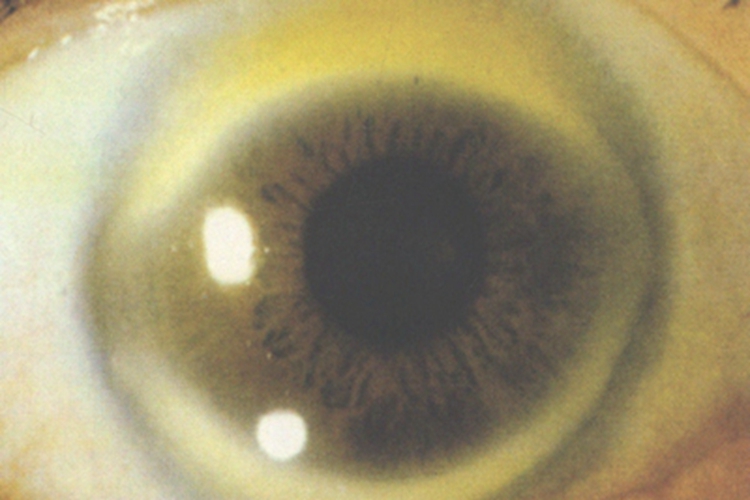

角膜老年环患者在临床上可表现为角膜边缘出现黄白色的斑块,像月牙一样,外侧边界较清,之后会逐渐发展融合成环状,患者多无自觉不适症状。